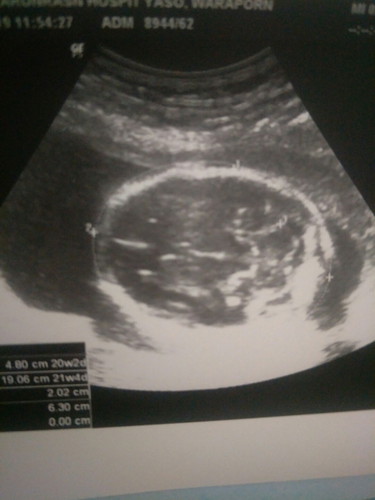

ถ่ายครั้งแรก

21สัปดาห์1วันตอนแรกถามหมออยากได้แบบรูปหมอบ่นว่าถ้าอยากรู้ละเอียดให้ไปซาว4มิติที่เอกชนบ่นๆๆๆแต่เราก็แค่อยากให้คนในครอบครัวเห็นด้วยหมดหวังคิดในใจว่าเดือนหน้าเก็บเงินไปซาวด์เสียเงินที่อื่นแต่พอเสดกลับมาบ้านเปิดดูหมอถ่ายมาให้ดีใจมากถึงจะดูไม่ค่อยออกว่าอะไรอยู่ตรงไหนแต่ดีใจที่สุดถึงจะแค่ครั้งเดียวก็ตาม?❤#อยากขอบคุณหมอค่ะ?แม่ๆท่านไหนถ่ายเก็บไว้ทุกเดือนบ้างค่ะ